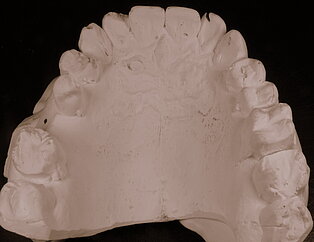

Ganzheitlich Zahntechnik

Keine Metalle im Mund

Keramik auf Metall

Keramikstufen

Nichtedelmetal NEM und Keramik